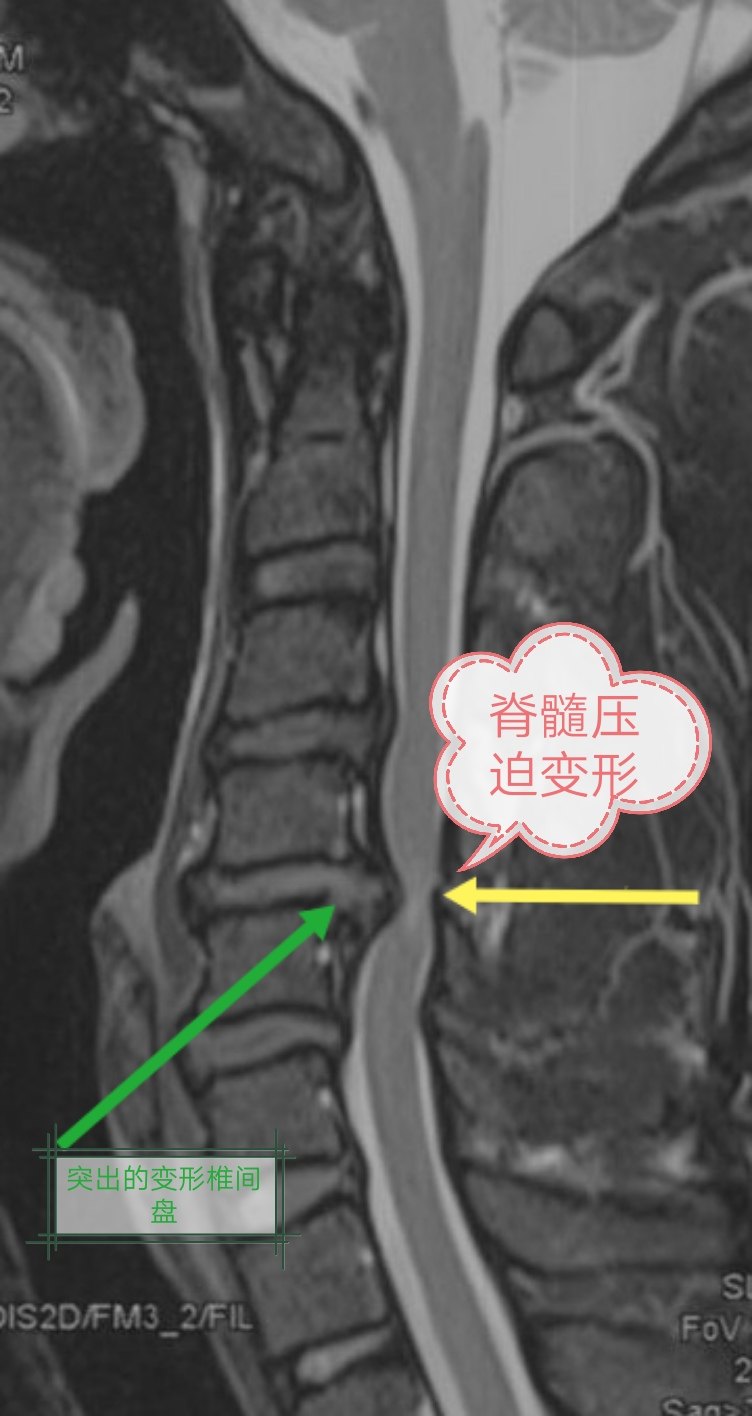

出现以上症状,应尽快找骨科(脊柱外科)医生就诊。拍颈椎X线片和MRI检查,不建议做CT检查(CT不能很好显示脊髓和神经,CT只是明确是否有骨赘)。颈椎X线片出现椎体有骨刺,颈椎变直甚至出现反弓。颈椎MRI显示椎间盘变性突出(图1),椎管内白色的脑脊液被阻断,脊髓和/或神经被压迫移位变性(图2),严重出现脊髓局部变白,这提示神经变性坏死(图3)。